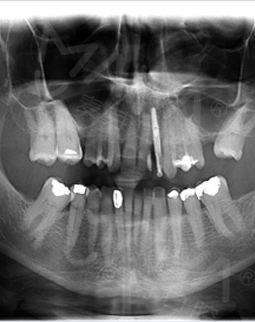

2016年4月 牙槽骨严重缺损,不适合一期种牙

来到深圳,多方寻医,一个医生朋友告诉我,这个只有到麦芽找郑苍尚院长,他能做。“我有6个月一直没有牙齿,我要我的牙齿。”这是我见到郑院长后说的第一句话,在麦芽流程很顺利,经过拍片检查后,郑院长说我剩余残根反复发炎松动,牙槽骨受损严重,影响咀嚼功能,只能拔除残根后需引导骨组织再生,不能一期种牙....很专业的词我不太懂,但是他能处理我就放心了!

在郑院长的建议下,我选择了诺贝尔植体,种植牙还需要骨粉骨膜,大致了解了种牙的流程,我很满意。